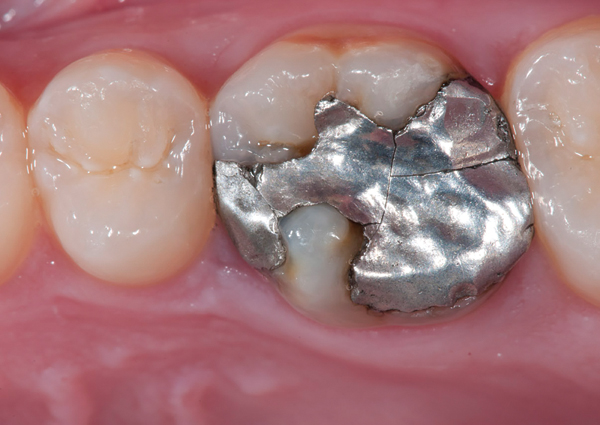

Fig 9. Preoperative view (Fig 9), preparation with composite block-out restoration (Fig 10), and final cementation of CL-IIb material (Fig 11) (final ceramic contour and stain by Steve Lee, CDT, MDC).

Figure 9

Fig 10. Preoperative view (Fig 9), preparation with composite block-out restoration (Fig 10), and final cementation of CL-IIb material (Fig 11) (final ceramic contour and stain by Steve Lee, CDT, MDC).

Figure 10

Fig 11. Preoperative view (Fig 9), preparation with composite block-out restoration (Fig 10), and final cementation of CL-IIb material (Fig 11) (final ceramic contour and stain by Steve Lee, CDT, MDC).

Figure 11